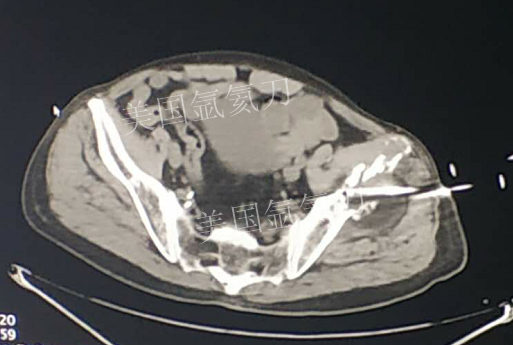

73岁臀部氩氦刀冷冻消融

发布人:美国氩氦刀技术官方网站    发布时间:2019/2/21 13:51:52